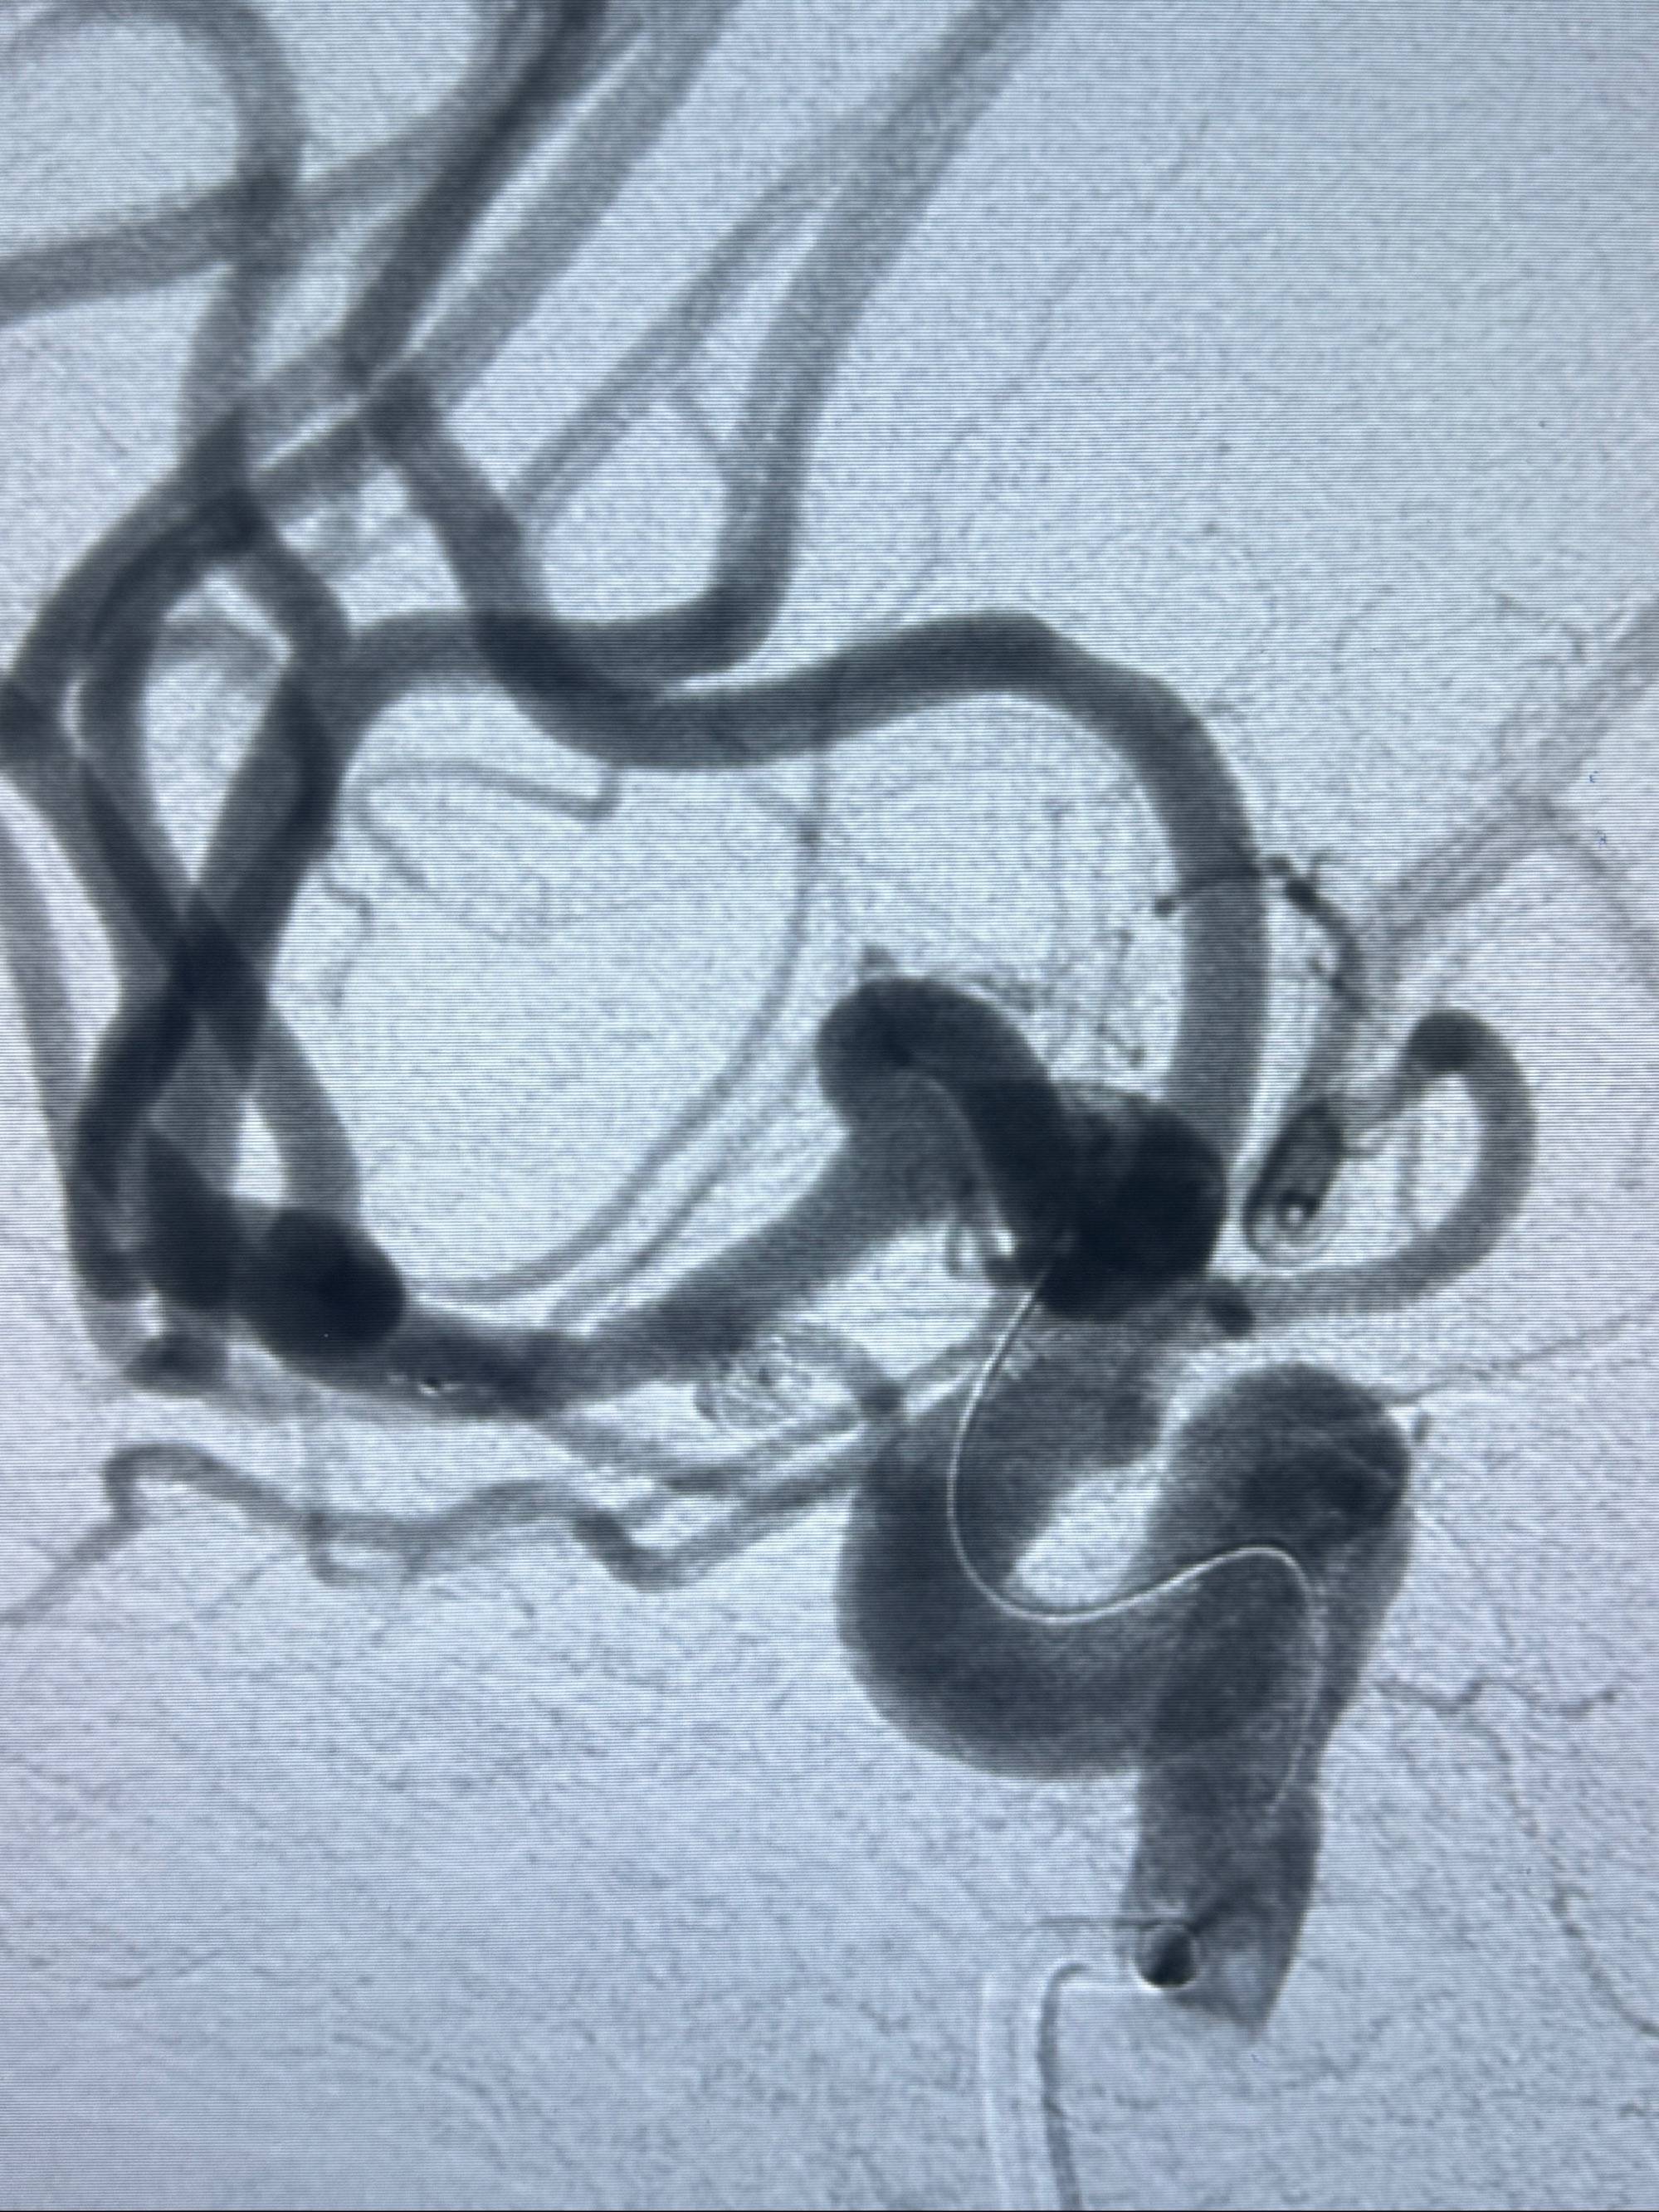

2023-11-24DSA:右侧大脑中动脉下干起始部动脉瘤,约2.3*2.5mm,形态规则

2023-12-04全麻下行支架辅助治疗

S-AB4-20mm